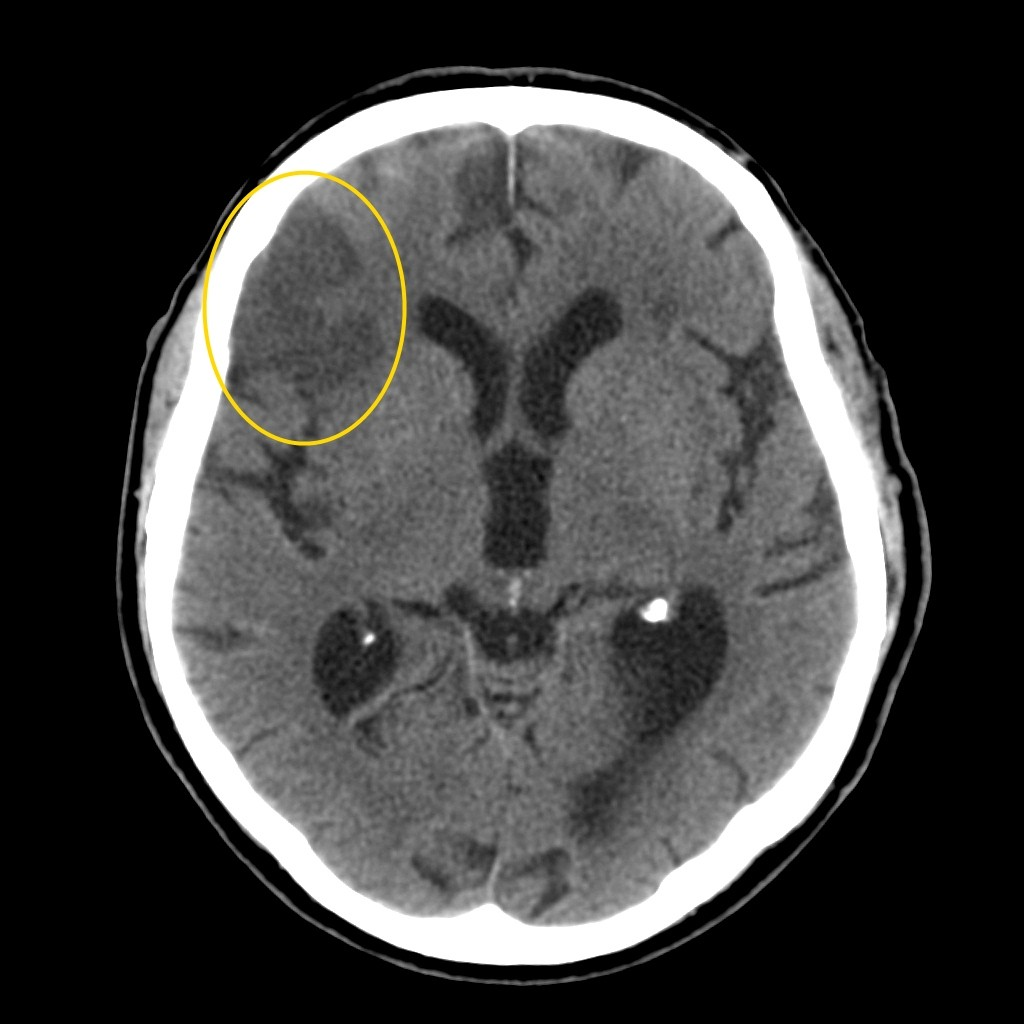

Компьютерная томография (КТ) и магнитно-резонансная томография (МРТ) — наиболее важные диагностические исследования при инсульте. КТ в большинстве случаев позволяет чётко отдифференцировать «свежее» кровоизлияние в мозг от других типов инсультов, МРТ предпочтительнее для выявления участков ишемии, оценки распространённости ишемического повреждения.

Ишемический инсульт. КТ.

Думаю, разница понятна. Особенно для начинающих. Все просто: Геморрагический - светлое пятно. Ишемический - темное.